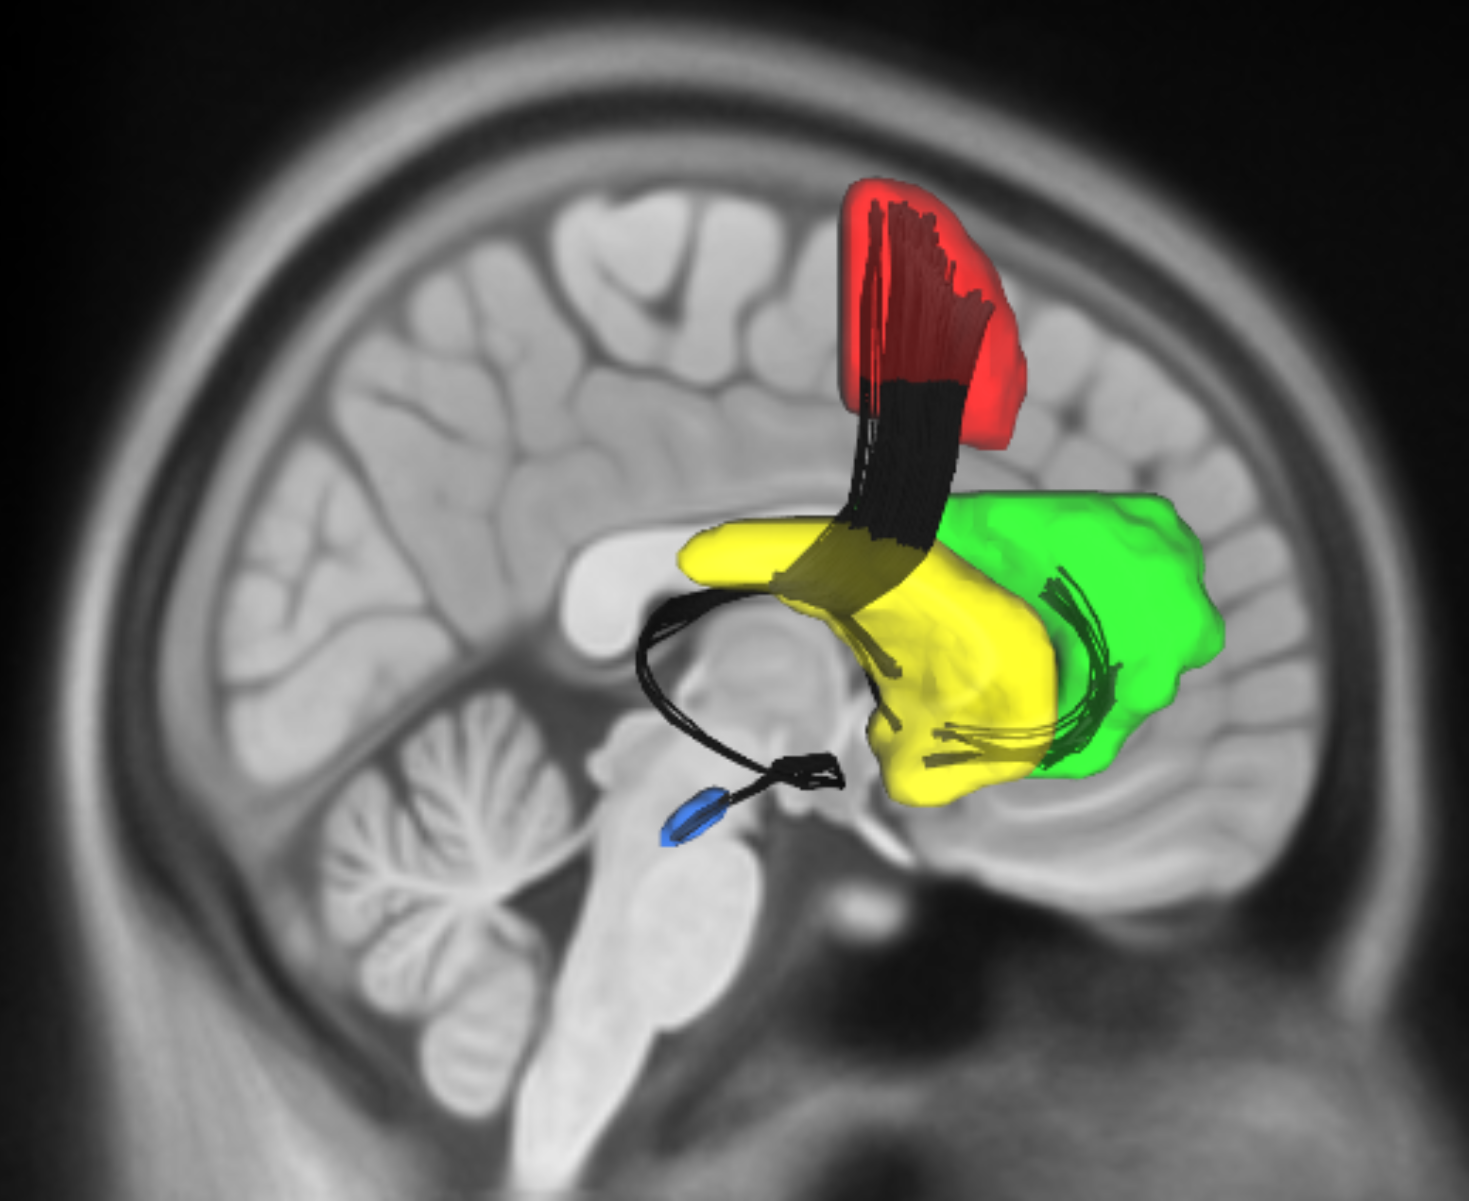

How does the brain automate actions across different systems (motor, emotional, physiological)? And how is habitual control affected by conditions like Parkinson's disease, where dopamine loss can disrupt everyday behaviors (e.g., writing)? Our goal is to understand the neural processes behind habitual actions and what happens when they break down.

We look at how key regions (e.g., prefrontal cortex, striatum) support self-regulation, especially under the influence of reward and emotion. We also develop models to understand how people learn and control stimulus-response associations, and examine cases where cognitive control fails, such as in impulsivity and brain lesions.